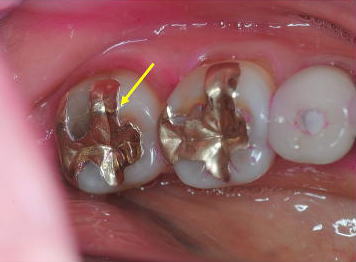

■症例1:酸食症 Acid Erosion

患者:54歳、女性。

当クリニックで装着したインレーが島状に浮き上がっている。(周囲のエナメル質の溶解)。6ヵ月間、就寝前に酸性水(通信販売)でうがいをしていた。使用した“強酸性水”のpH3.0以下。失ったEnamel質は戻らない